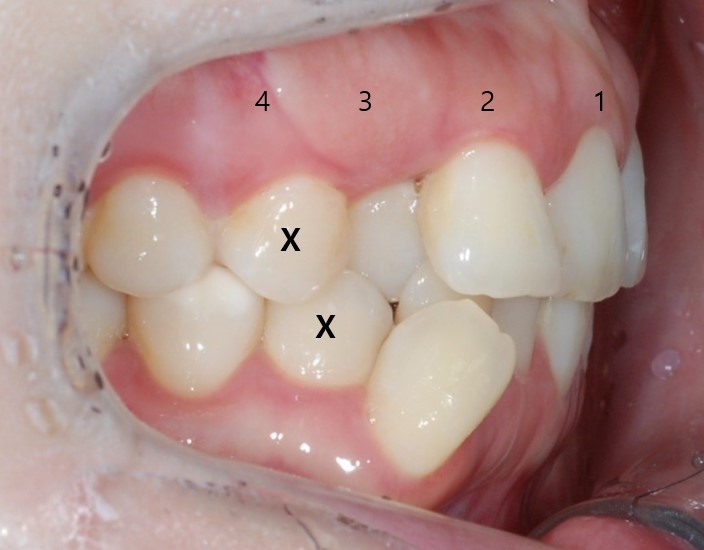

환자분의 동의를 구하고

오른쪽 위, 아래

각 4번째 치아를

발치했습니다.

발치했던 공간

어디 갔나요..

원래 치아가 있었던것 맞죠???

잠실새내역인비절라인의

클린체크 예상대로

치아들이 아주 잘 움직였습니다.

Tracking ClinCheck

Unilateral 1st premolar extraction with Invisalign